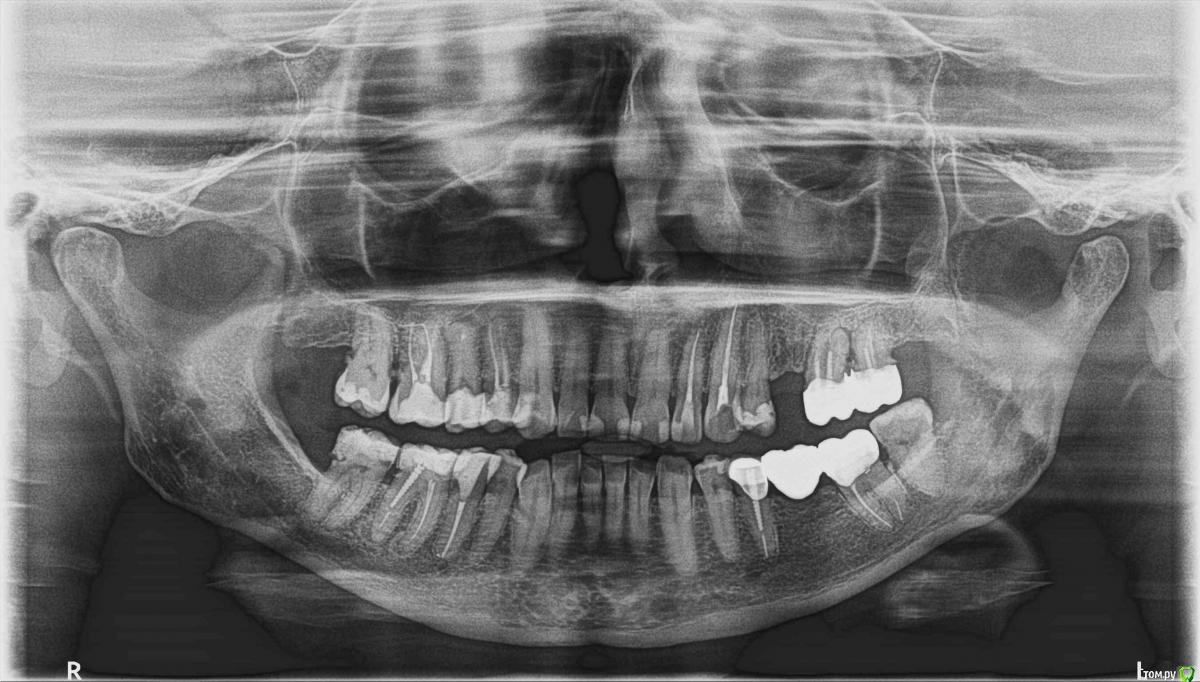

NaMe Опубликовано 6 февраля, 2020 Поделиться Опубликовано 6 февраля, 2020 (изменено) Здравствуйте, уважаемые специалисты!Очень нужен ваш совет. Мне 63 года. В течение пяти лет лечила постменопаузальный остеопороз: 3 года - бисфосфонатами (бонвива - внутривенно 1 раз в 3 месяца), затем 2 года - деносумаб (2 раза в год подкожно). С сентября сделала перерыв в связи с зубными проблемами.В конце декабря пришлось удалить 27-й зуб. Заживление идет, но медленно. Стоит вопрос и об удалении 26-го зуба. Предложены следующие варианты: 1. Попытаться сохранить 26-й зуб под самой простой коронкой в надежде, что он какое-то время простоит и его можно будет частично использовать для жевания. 2. Сделать мостик между 24-м и 26-м зубом.Но 24-й зуб живой. Стоит ли его депульпировать и препарировать под такую ненадежную с точки зрения перспектив 26-го зуба конструкцию? 3. Удалять 26-й зуб и делать съемный протез. Возможно ли и целесообразно ли это именно в моем случае? Не приведет ли это к еще бОльшим осложнениям, чем отсутствие жевательных зубов? И если возможно, то какой протез в принципе предпочтительнее в моем случае - при одностороннем концевом дефекте верхней челюсти? 4. Некоторые специалисты говорили, что через год после отмены бисфосфонатов якобы можно даже делать имплантацию. Я же читала, что прием бисфосфонатов в анамнезе является абсолютным противопоказанием к имплантации. Через какое время после удаления зуба вообще можно начинать что-то предпринимать? Очень сложно найти специалиста, который был бы знаком с особенностями таких пациентов, как я. Поэтому я очень надеюсь на вашу помощь.Буду признательна за высказанные мнения!Прилагаю ссылку на КТ.https://cloud.mail.ru/public/RXz8/5iXjka7Y4 Приложила еще и обычный панорамный снимок. Он тоже нестарый. Разница в том, что 27-й зуб был удален позже. Изменено 6 февраля, 2020 пользователем NaMe Ссылка на комментарий

NaMe Опубликовано 11 февраля, 2020 Автор Поделиться Опубликовано 11 февраля, 2020 (изменено) http://forum.stom.ru/topic/28667-bifosfonaty-ogranichennyj-osteomielit/Еще раз перечитала статью. Все же сумела продраться сквозь профессиональные премудрости и найти некоторые важные ответы на свои вопросы. Благодарю! Может быть, кто-то из специалистов найдет возможным посмотреть мою ортопантомограмму и ответить лишь на один вопрос другого плана. 47-й зуб - живой. С самой дальней стороны там есть кариес? Если да, то насколько этот кариес глубок, чтобы дать внезапную острую боль в ближайшее время - 6-8 месяцев? В настоящее время зуб не беспокоит вообще никак. Не хочется его перелечивать раньше времени. Но летом я планирую некоторое время быть в местах, где сложно будет получить экстренную стоматологическую помощь вообще, а тем более качественную. Поэтому есть опасение попасть в тяжелую ситуацию.Буду признательна за пояснения! Изменено 11 февраля, 2020 пользователем NaMe Ссылка на комментарий

red_butler Опубликовано 12 февраля, 2020 Поделиться Опубликовано 12 февраля, 2020 4.7 «живой», кариес есть, лечите и восстанавливайте зуб коронкой Ссылка на комментарий

NaMe Опубликовано 12 февраля, 2020 Автор Поделиться Опубликовано 12 февраля, 2020 Спасибо за ответ! Правильно ли я поняла, что зуб может заявить о себе в любой момент и с его лечением лучше не затягивать? Ссылка на комментарий

red_butler Опубликовано 12 февраля, 2020 Поделиться Опубликовано 12 февраля, 2020 Спасибо за ответ! Правильно ли я поняла, что зуб может заявить о себе в любой момент и с его лечением лучше не затягивать?правильно Ссылка на комментарий